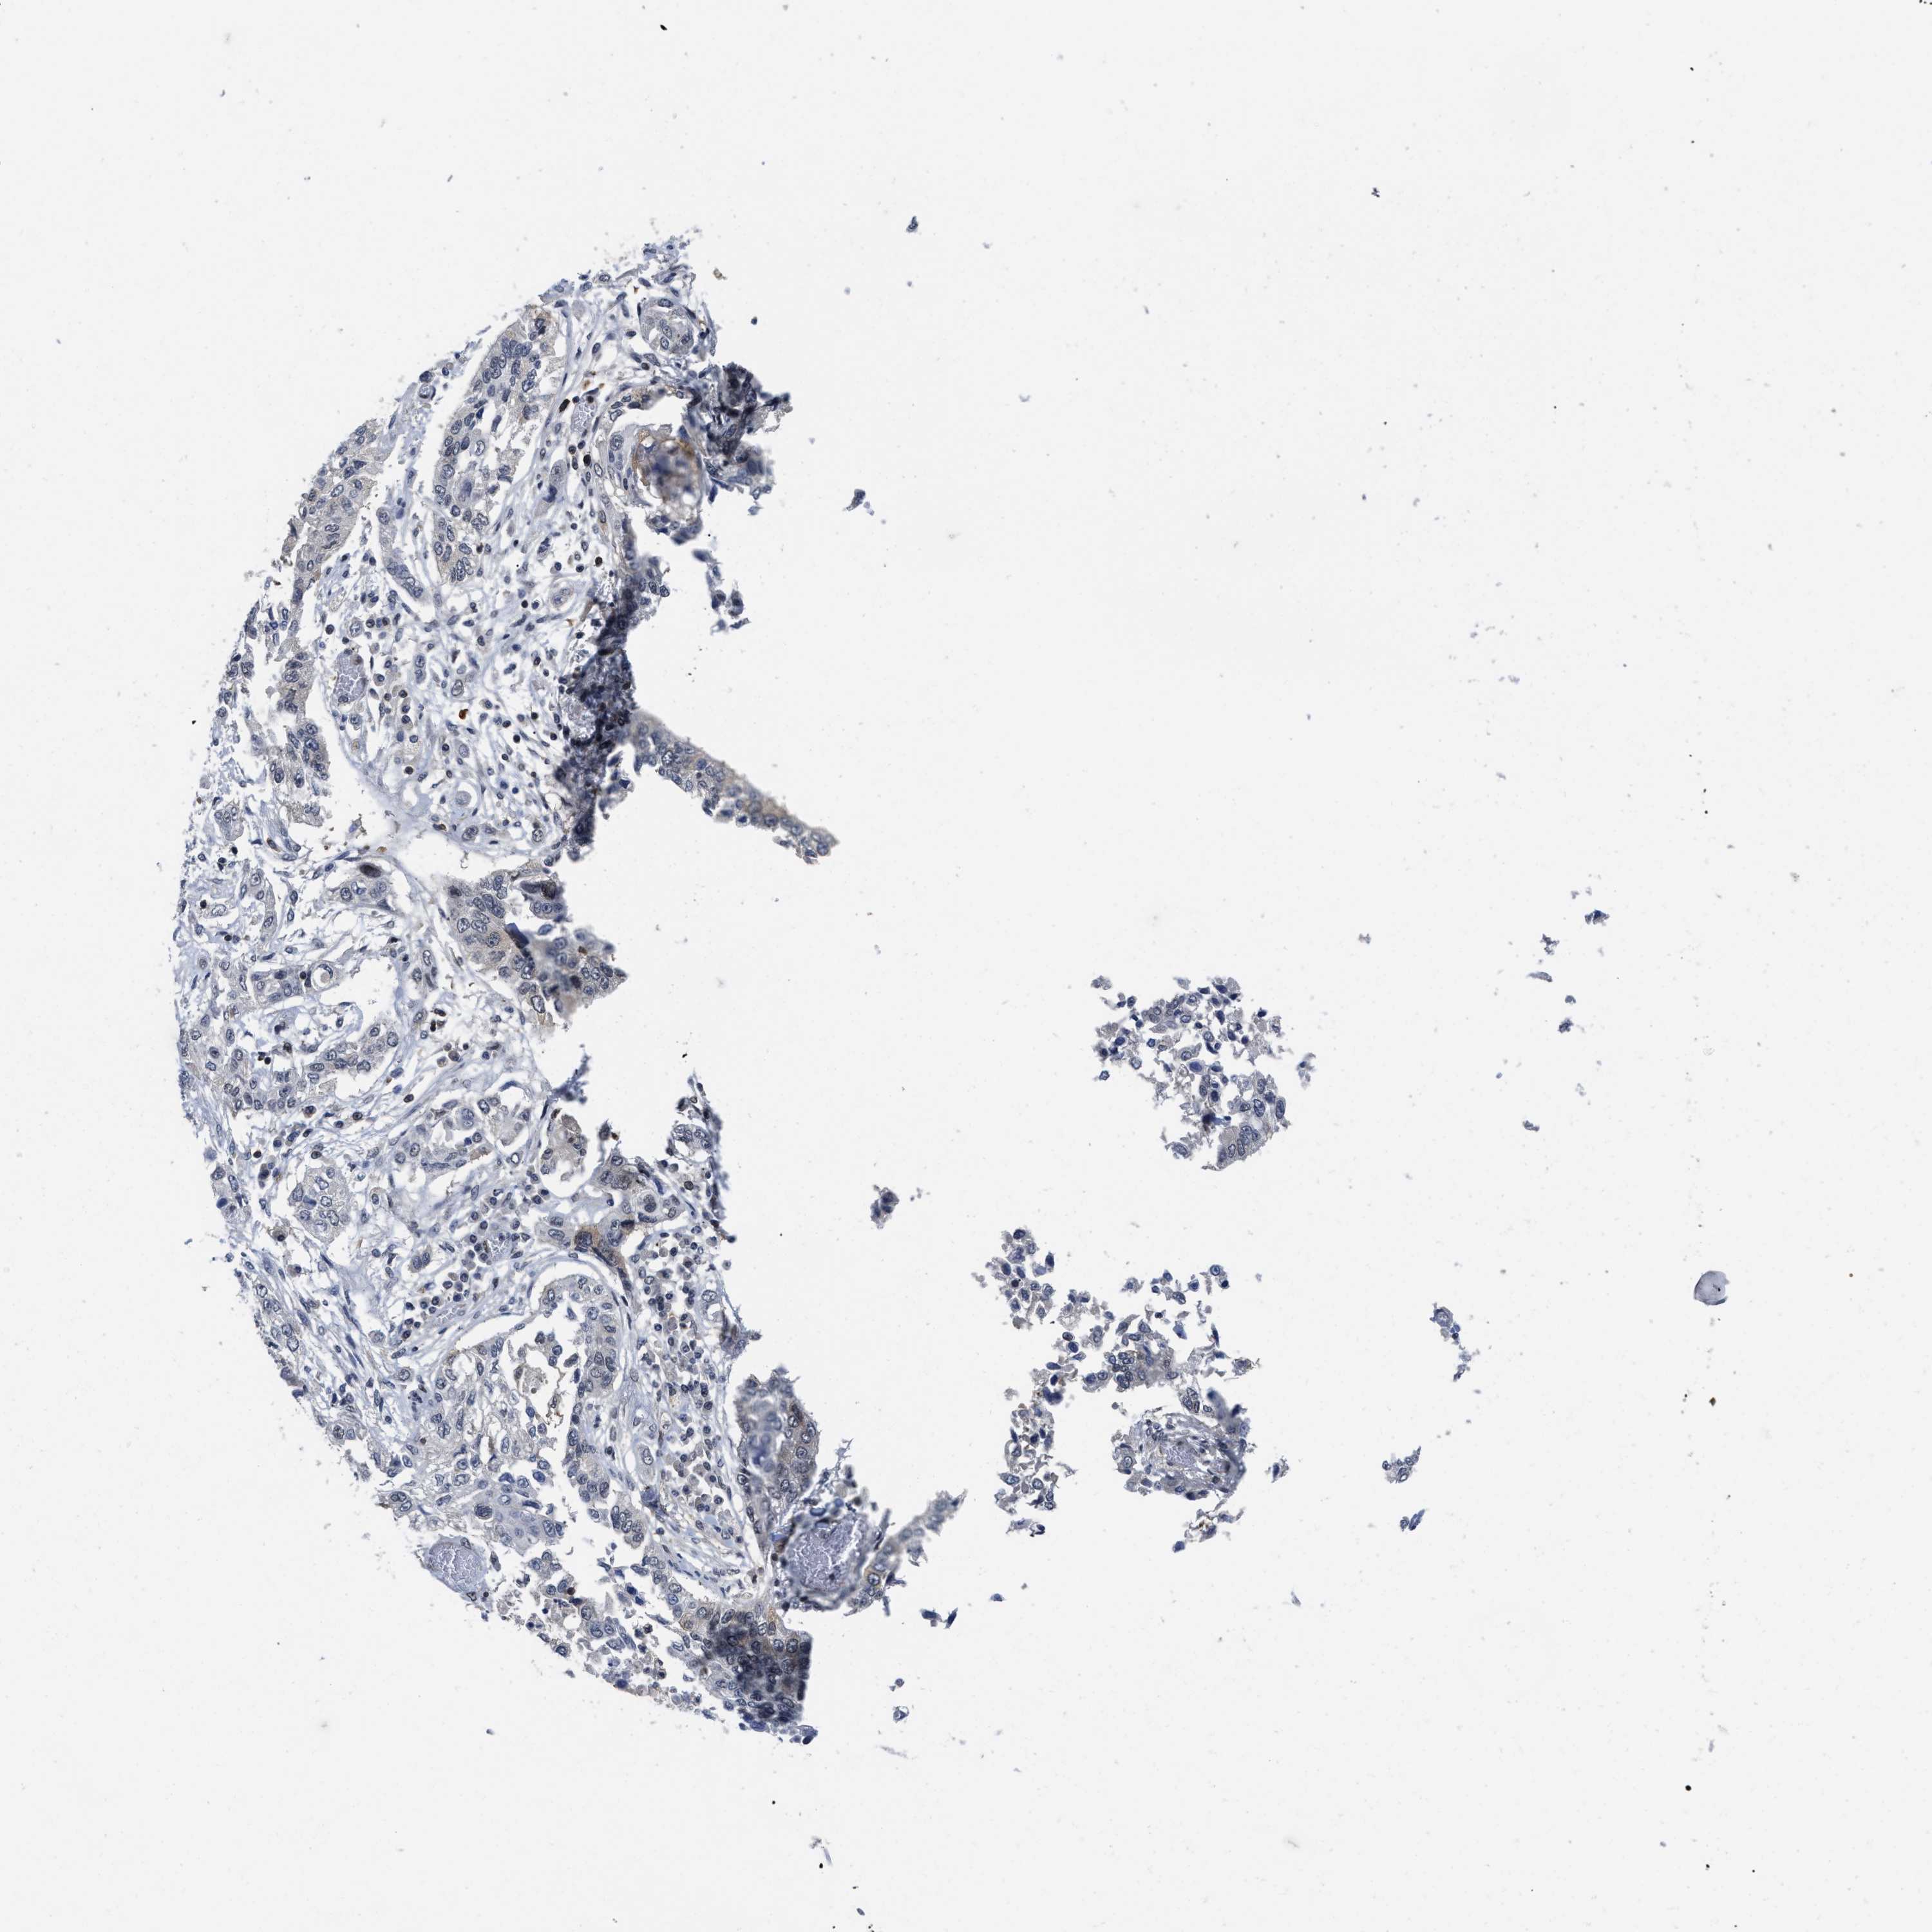

CANCER LUNG CANCER Show tissue menu